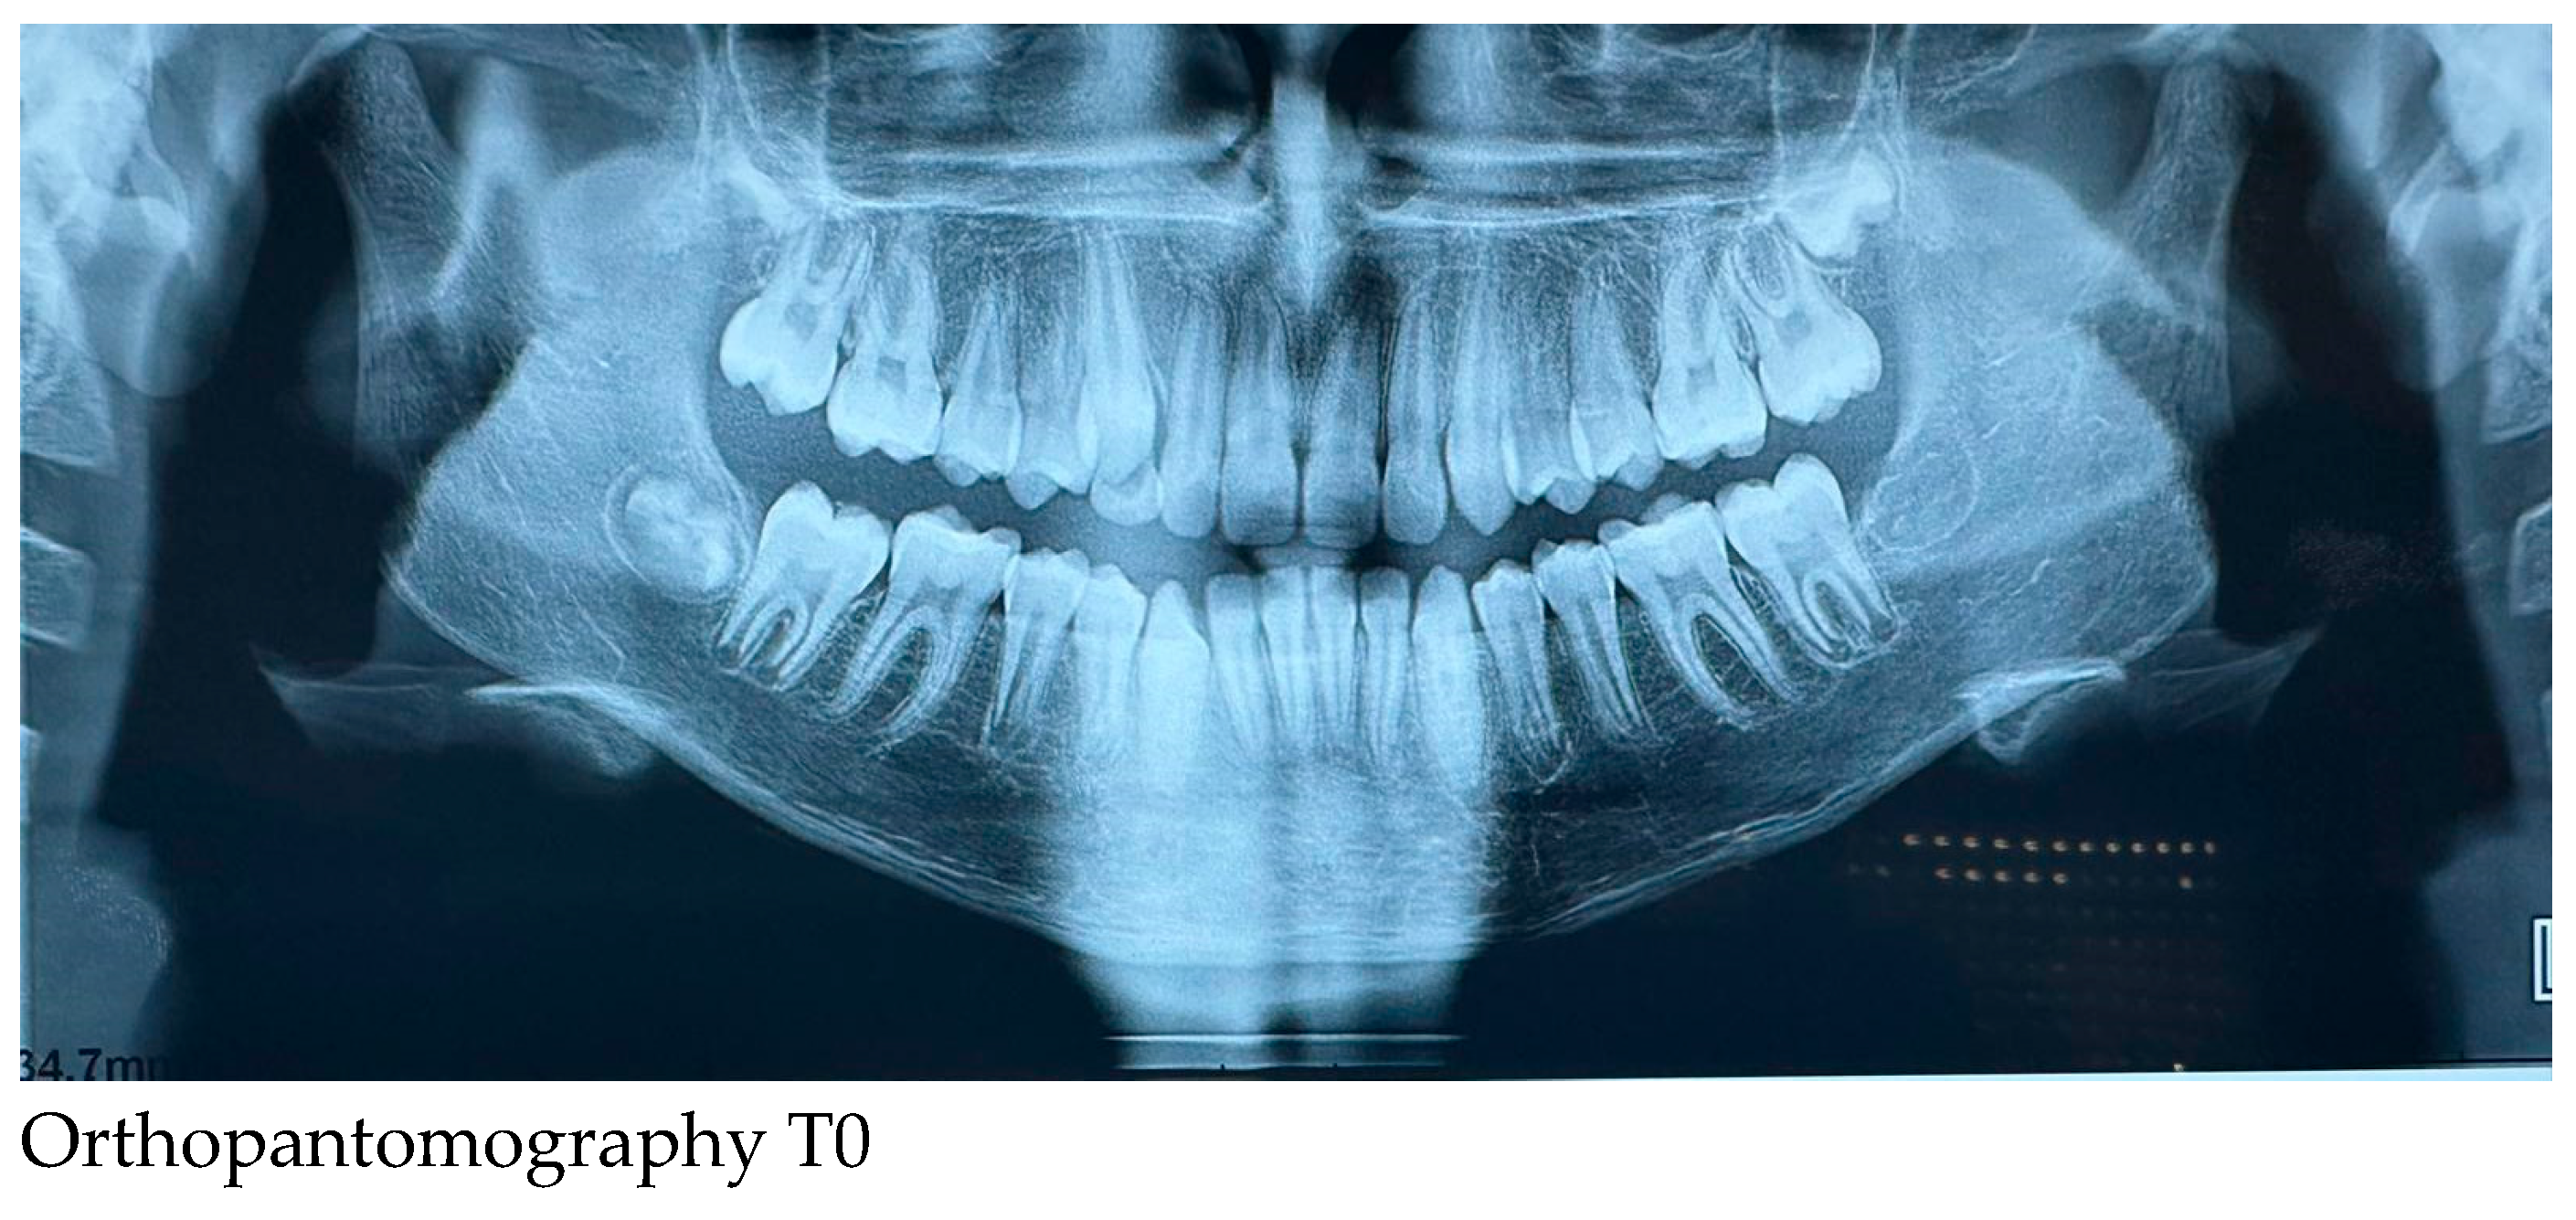

2.3. Initial and Post-Treatment Records

Orthopantomography of the dental arches and lateral skull teleradiography taken before (T0-at the start of treatment) and at the end of Herbst-RPE therapy (T1-after removal of braces) were evaluated. The subject was positioned in the natural head position, with the teeth in centric occlusion and with the lips slightly closed for lateral cephalometric radiographs.

Radiographs such as orthopantomography and lateral skull teleradiography are provided. The cephamolecular analysis shows some changes: improvement of the Wits index, growth of the mandibular ramus while keeping the position of the lower incisors almost unchanged (

Table 1).